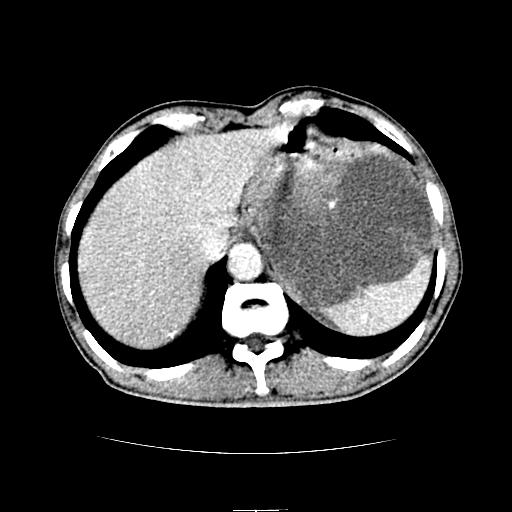

标题: CT6969:腹部,某男 34岁,腹痛治疗半月无效 [打印本页]

标题: CT6969:腹部,某男 34岁,腹痛治疗半月无效

左上腹胃、脾及胰腺间巨大囊性占位性病变,内见多数薄隔,有轻度强化,明显占位效应。左肾见一小囊肿。

考虑:1、左上腹巨大囊肿(可能来源于胰腺)。

2、左肾小囊肿。